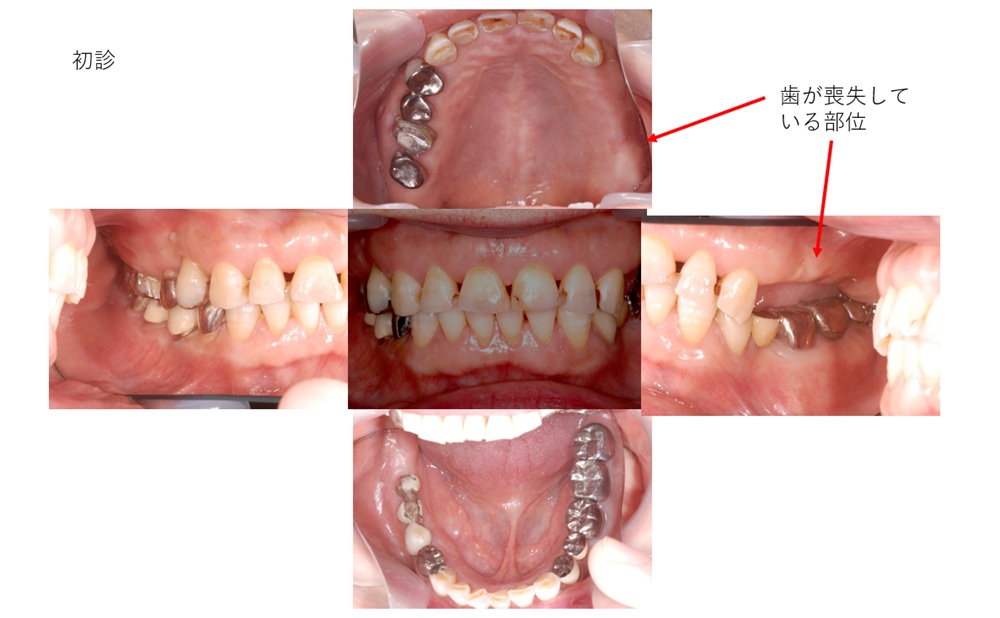

お口の中を拝見する。

写真のように、左上奥歯がありません。

歯が全体的に摩耗しております。

噛む力が強い?また、歯ぎしり、食いしばりもある可能性があります。

それが、原因で、歯が無くなったのではと推察されます。